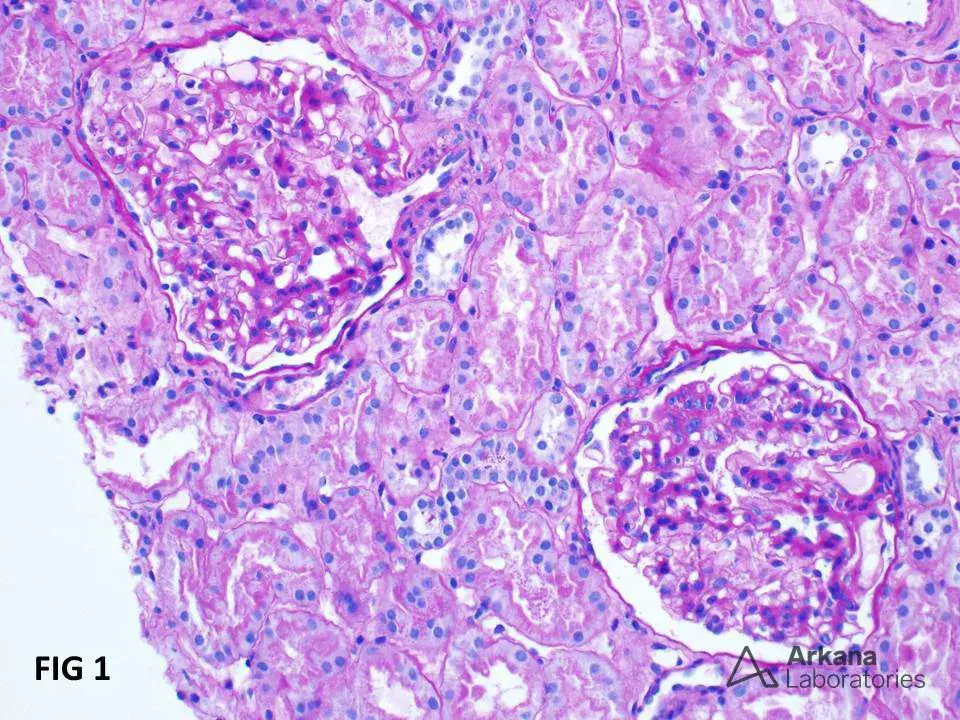

Hiperlipidemia na Nefropatia Membranosa: Um novo olhar que impacta no tratamento

A dislipidemia na Nefropatia Membranosa sempre foi tratada como dano colateral da síndrome nefrótica. Essa revisão muda a pergunta — e muda o que fazemos com ela.